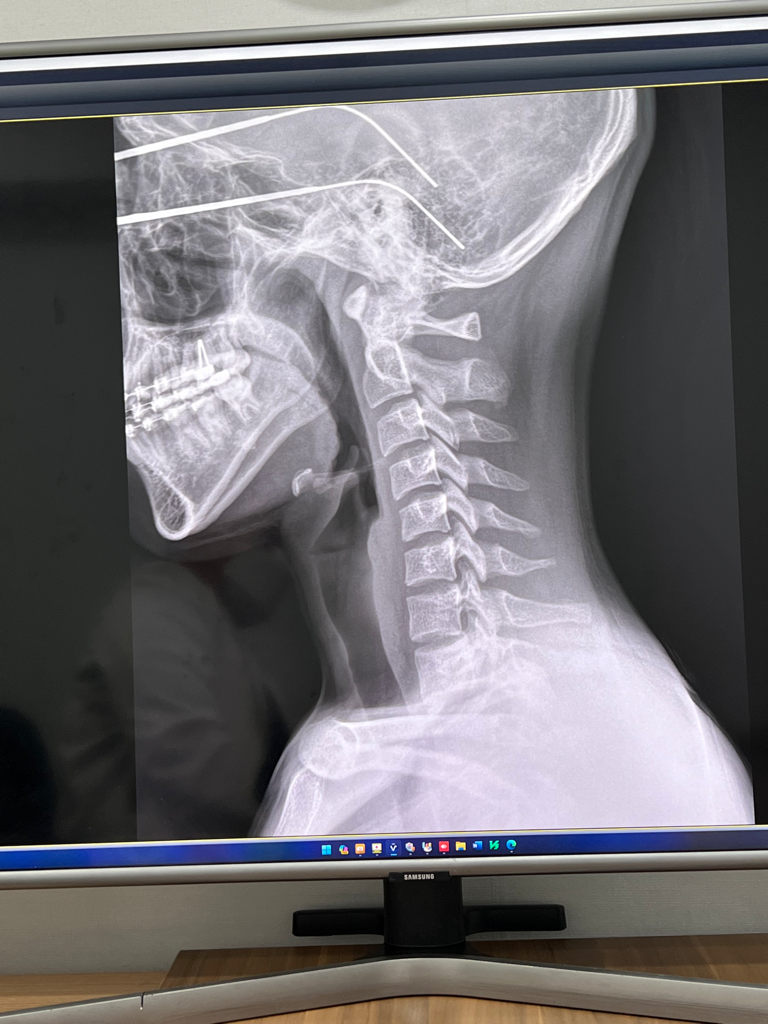

역c자목 어느정도 기간만에 치료되나요?

역c자목증후군

역c자목 증후군을 갖고있다고 진단받았습니다

당일 1회 물리치료를 받았고 1-2주 이후인 현재 비슷한 증상을 겪는 중입니다 정상적인 커브형 목으로 돌아가려면 병원을 몇 회 어느정도 기간동안 다녀야할까요

• 1번 째 사진

역c자목의 원인이 되는 자세를 교정하는데에 일반적으로 3개월 정도의 시간이 소요됩니다. 완전히 정상적인 c자 커브를 회복하는 데에 소요되는 시간은 개인차가 커서 정확히 말씀드리기는 어렵습니다만, 안좋은 자세가 수년간 유지되어 발생한 증상인 만큼 돌아가는 데에도 수년의 시간이 소요될 수 있습니다.

좌우비대칭 역시 틀어진 자세를 교정하시는 것이 중요하고, 재활의학과 등 다양한 의료기관에서 진료를 제공하니, 사전에 문의해 보시는 것이 좋겠습니다.